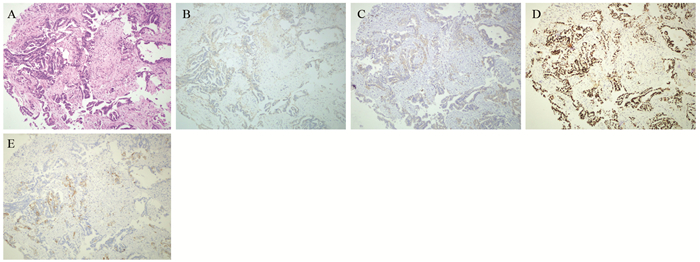

在ST-PACS医学图像工作站(北京思创贯宇科技开发有限公司)上选取肿瘤最大层面相邻的三个层面,利用自由形标记工具在ADC图上手工绘制ROI,在b=1 000s/mm2下测量平均ADC值(ADCmean)、最小ADC值(ADCmin),每个层面测量3次,并计算平均值。相对ADC值(rADC)=瘤体区ADC值/对侧脑白质ADC值,见图 1。

![]() 图 1 少突胶质细胞瘤(WHOⅢ级;IDH-1突变/1p19q共缺失)MRI和病理学表现Figure 1 MRI and pathological manifestations of oligodendrocytoma (WHO gradeⅢ) with IDH-1 mutation/1p19q co-deletionA, B: the lesions in the right temporal-parietal lobe showed heterogeneous low signal and high signal on T1WI and T2WI, respectively; C, D: DWI presented as an inhomogeneous equal-slightly higher signal (mild diffusion restricted) (C) and ADC map showed an inhomogeneous low-slightly higher signal (D); E: the measurement method of ADC value to select three ROI (10-20 mm2) in lesions and take their average values as well as select the contralateral normal brain white matter to calculate rADC; F: tumor cells were arranged in diffuse pieces, the nucleus with obvious atypia was large, and numerous necrotic regions were found in the lesions (HE ×200).

图 1 少突胶质细胞瘤(WHOⅢ级;IDH-1突变/1p19q共缺失)MRI和病理学表现Figure 1 MRI and pathological manifestations of oligodendrocytoma (WHO gradeⅢ) with IDH-1 mutation/1p19q co-deletionA, B: the lesions in the right temporal-parietal lobe showed heterogeneous low signal and high signal on T1WI and T2WI, respectively; C, D: DWI presented as an inhomogeneous equal-slightly higher signal (mild diffusion restricted) (C) and ADC map showed an inhomogeneous low-slightly higher signal (D); E: the measurement method of ADC value to select three ROI (10-20 mm2) in lesions and take their average values as well as select the contralateral normal brain white matter to calculate rADC; F: tumor cells were arranged in diffuse pieces, the nucleus with obvious atypia was large, and numerous necrotic regions were found in the lesions (HE ×200).1.4 统计学方法